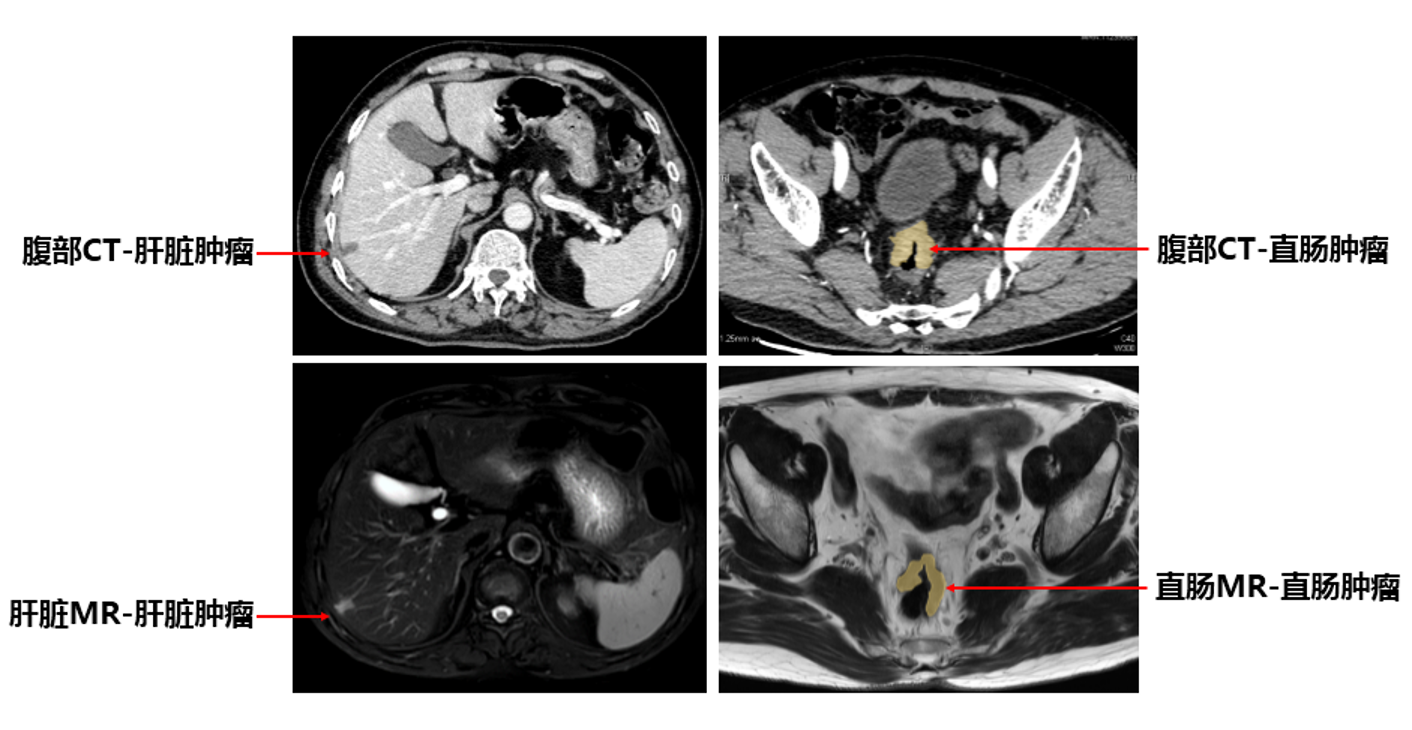

清华长庚多学科联合 为晚期肿瘤患者抢回来一个春节